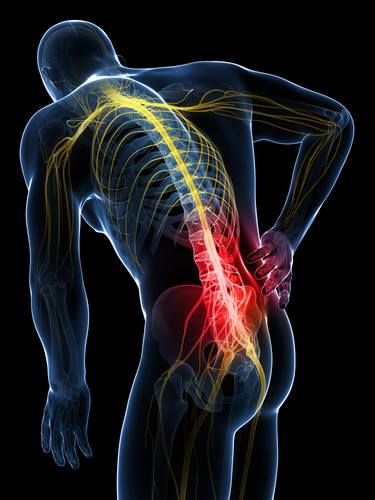

Sakit pinggang merupakan salah satu keluhan fisik yang paling umum dialami oleh orang dewasa, namun sayangnya sering kali dianggap sebagai konsekuensi normal dari kelelahan bekerja atau bertambahnya usia. Banyak orang memilih untuk mengabaikan rasa tidak nyaman ini dengan harapan rasa sakit akan hilang dengan sendirinya setelah beristirahat. Padahal, pinggang adalah pusat tumpuan tubuh yang menyokong beban saat kita berdiri, duduk, maupun bergerak. Mengabaikan sinyal nyeri pada area ini tanpa memahami akar permasalahannya dapat menyebabkan kondisi tersebut berkembang menjadi masalah kronis yang membatasi mobilitas dan kualitas hidup secara signifikan.

Salah satu penyebab utama yang sering terlewatkan adalah kebiasaan postur tubuh yang buruk saat duduk dalam durasi yang lama. Di era digital ini, banyak orang menghabiskan waktu berjam-jam di depan layar dengan posisi punggung yang melengkung atau leher yang condong ke depan. Posisi ini memberikan tekanan statis yang berlebihan pada diskus intervertebralis dan otot-otot di sekitar tulang belakang bawah. Jika dilakukan terus-menerus, otot pinggang akan mengalami ketegangan konstan atau spasme, yang jika tidak segera ditangani dengan teknik manipulasi otot yang tepat, akan mengubah struktur keseimbangan tubuh dan memicu nyeri yang menjalar hingga ke kaki.

Selain masalah postur, kelemahan pada otot inti atau core muscles juga menjadi faktor tersembunyi di balik nyeri pinggang yang berulang. Banyak yang tidak menyadari bahwa kekuatan otot perut dan punggung bawah berfungsi sebagai “korset alami” yang melindungi tulang belakang. Ketika otot-otot ini lemah, beban tubuh tidak terdistribusi dengan merata, sehingga sendi dan ligamen di area pinggang harus bekerja lebih keras dari kapasitas aslinya. Kondisi ini sering kali diperparah oleh kurangnya aktivitas fisik atau teknik mengangkat beban yang salah, di mana seseorang cenderung menggunakan otot pinggang daripada otot paha, yang secara instan dapat memicu cedera otot akut atau bahkan saraf terjepit.

Faktor lain yang jarang disadari adalah pengaruh alas kaki dan distribusi beban pada kaki saat berjalan. Ketidakseimbangan pada tumpuan kaki dapat merambat naik hingga ke panggul dan pinggang, menyebabkan otot-otot di satu sisi tubuh bekerja lebih keras untuk menjaga keseimbangan. Oleh karena itu, penanganan sakit pinggang tidak bisa hanya fokus pada penghilang rasa sakit sementara. Diperlukan pendekatan yang menyeluruh untuk mengurai ketegangan jaringan lunak dan mengembalikan fungsi mekanik tubuh ke kondisi normal. Dengan mengenali penyebab-penyebab yang sering diabaikan ini, kita bisa lebih waspada dalam menjaga kesehatan tulang belakang sebelum keluhan kecil berubah menjadi kendala fisik yang serius.